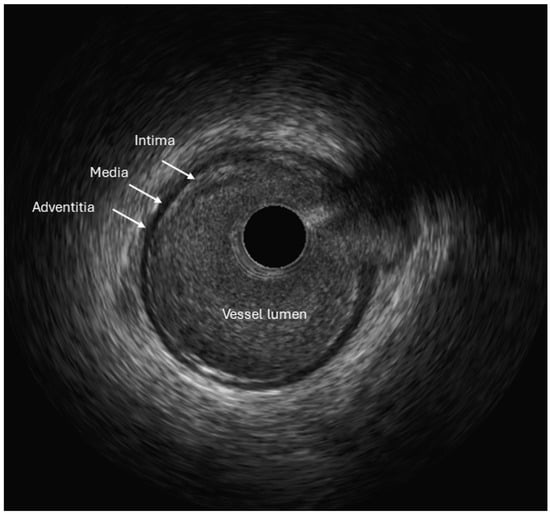

2.1. Intravascular Ultrasound (IVUS)